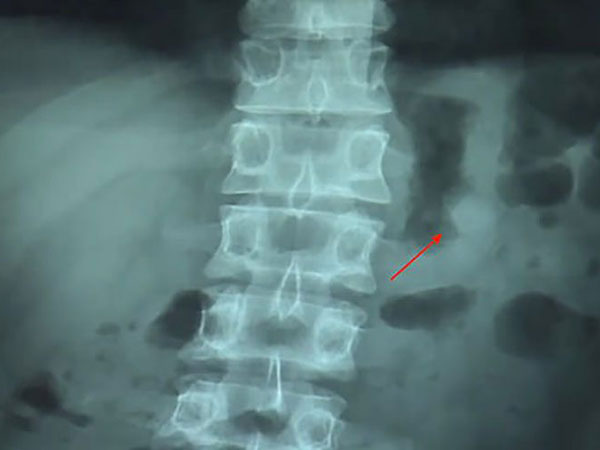

மருத்துவர் ஒருவரிடம் சென்று தன் பிரச்னையை கூறினார் ஸு. மருத்துவர், எக்ஸ் ரே எடுத்துப் பார்த்ததில், ஸுவின் செரிமான உறுப்புகளுக்குள் ஏர்பாட் இருப்பது தெரிய வந்தது.